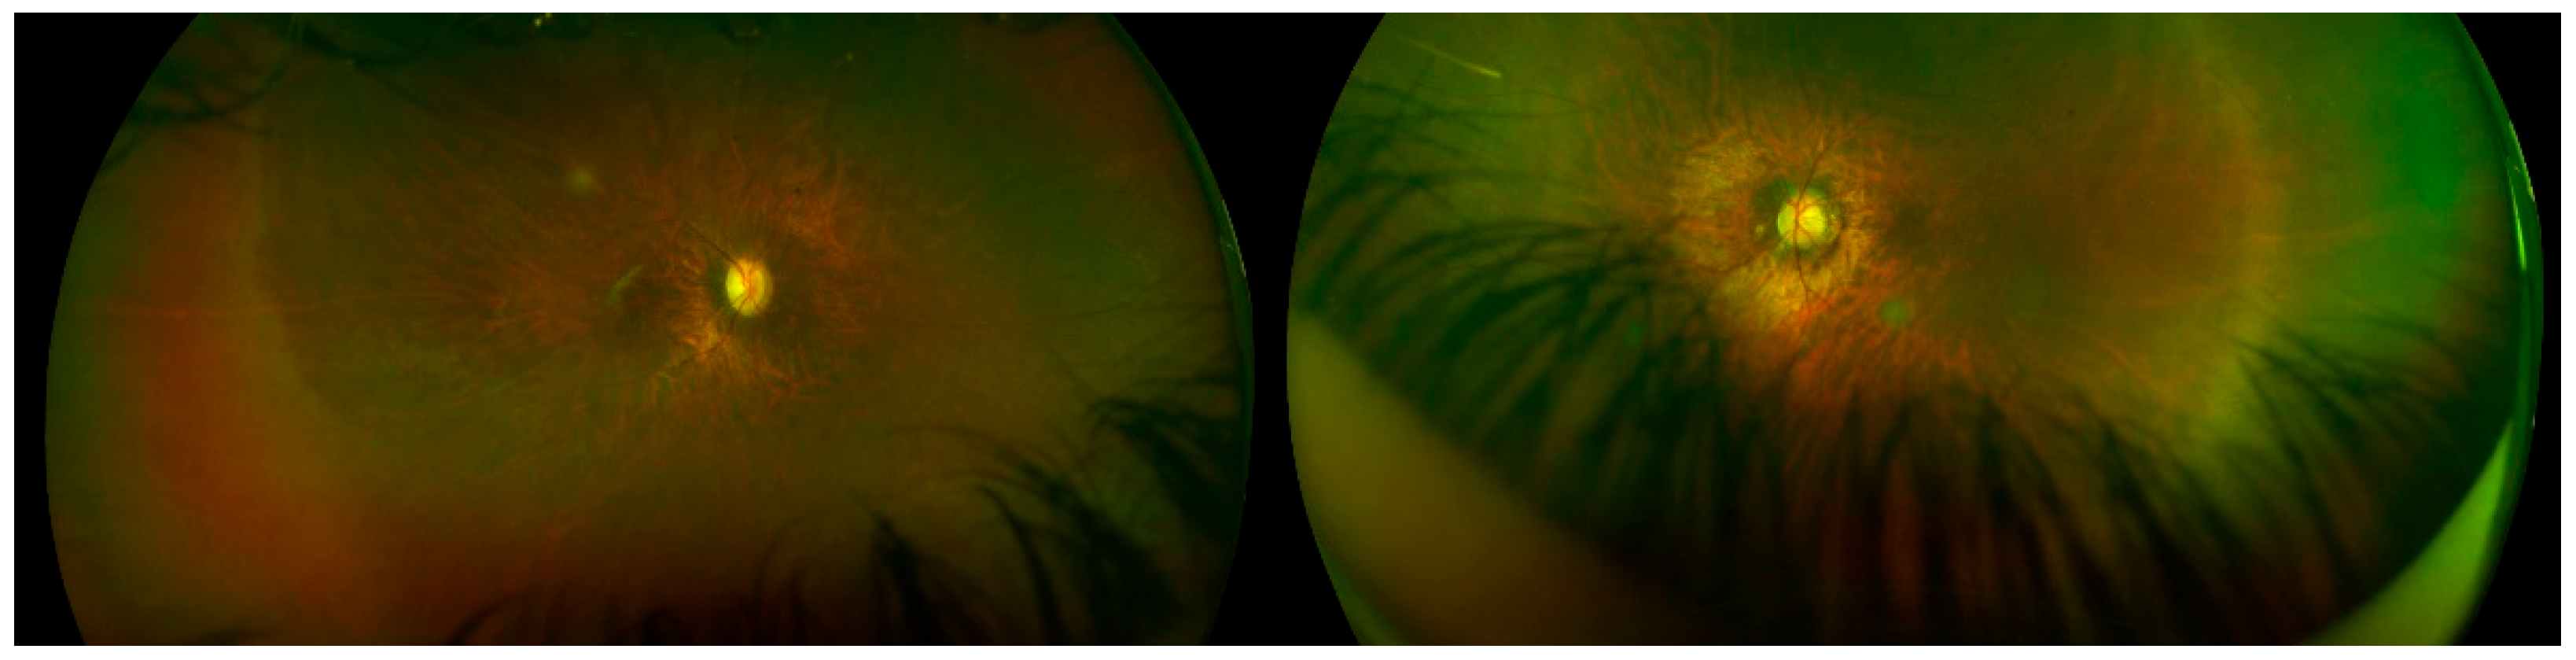

| OFT-00223 | F | 0.3 | 0.3 | 28.04 | 27.62 | Atrophic optic nerve | Atrophic optic nerve | −13.5 | −2.5 | −14.75 | −13 | −0.5 | −13.25 |

| OFT-00343 | EoHM | - | OPA1 | NM_130837.3 | c.1294G>A: p.Val432Ile | PM1, PM2, PP2, PP3, PP5 | LP | Missense | Hetero | AD | Yes | Paternal | Stewart et al., 2008 [32]; Yu-Wai-Man et al., 2011 [33] |